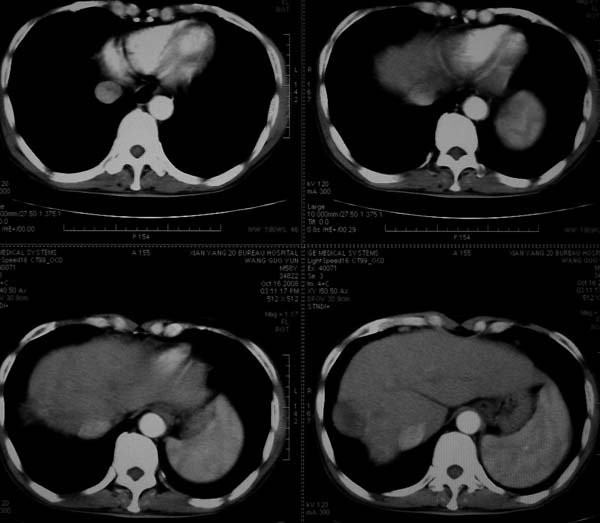

标题: CT16292:男,53岁,上腹部不适2月,B超发现肝内占位病变。 [打印本页]

标题: CT16292:男,53岁,上腹部不适2月,B超发现肝内占位病变。

肝脏体积变小,肝裂增宽,分布异常,肝尾叶增大,脾肿大,考虑肝硬化可能性大,右肝病灶呈现早期充盈,延迟强化考虑肝内胆管细胞癌可能,不除外血管瘤

肝叶比例失调,左叶增大,肝裂增宽,脾脏增大,门脉增宽,肝右叶包膜下多发结节样阴影,增强虽说强化幅度不大,但还是符合快进快出特点;考虑肝硬化、脾大、结节型肝癌。胆管细胞癌多有延时强化、肝包膜凹陷征、周围胆管扩张等特点,本例明显不符;故不考虑。